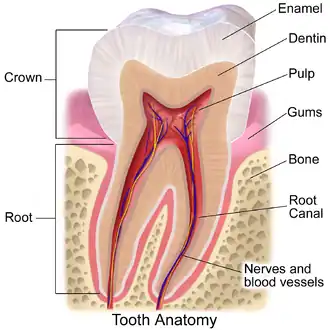

Cross-section of a tooth with gums labeled | |